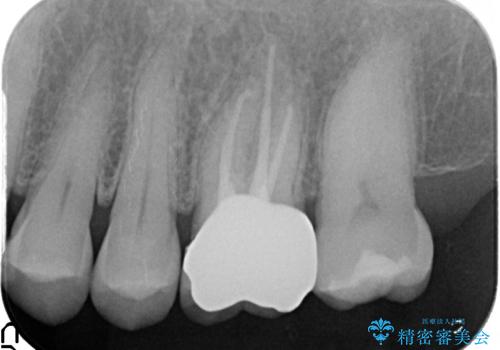

検査の結果歯の神経が死んでいたため根管治療を施し、症状が治まったのを確認後オールセラミッククラウンによる補綴を行いました。

- オールセラミッククラウン…¥100,000、仮歯…¥10,000、ファイバーコア…¥20,000費用は治療当時の料金となります

今回用いたオールセラミッククラウンはジルコニアフレームという白い素材の上にセラミックを盛っているため、審美性が非常に高いのが特徴です。

また、ジルコニアは人工ダイヤモンドの材料にも使われているほど高い強度を持っており、そのためオールセラミッククラウンは審美性だけでなく、奥歯やブリッジの補綴も可能とするクラウンです。